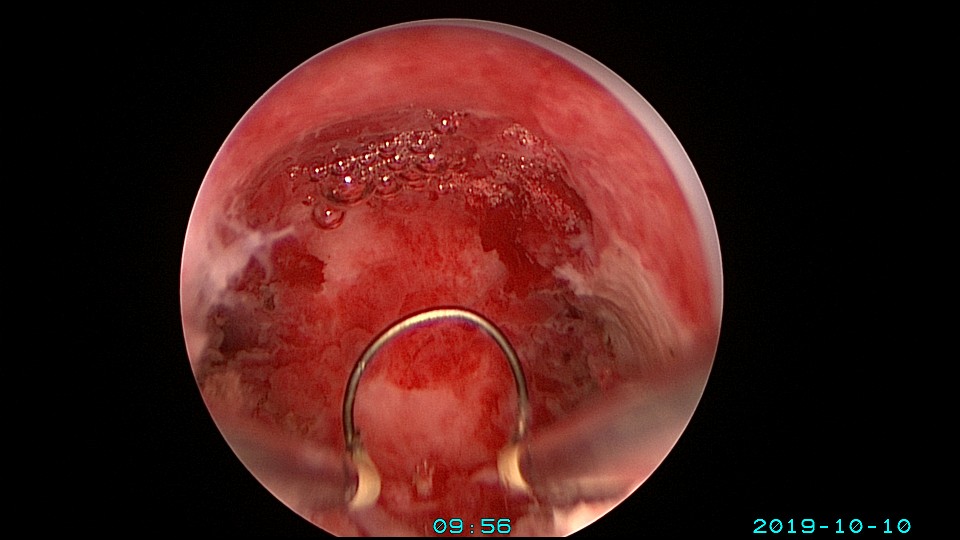

患者26岁,G1P0 ,2019年9月门诊宫腔镜检查发现宫腔重度粘连,2019年10月住院宫腔镜分粘,恢复宫腔形态,显露双侧输卵管开口。2019年11月宫腔镜二探取球囊,宫腔形态正常,双侧输卵管开口可见。2021年3月发现自然妊娠,后因先兆流产、胎心弱在当地医院险些清宫终止妊娠,病人电话咨询我,嘱病人千万不要急着清宫,立即到我院复查,心管搏动良好,住院保胎成功,2021年11月,39周孕剖宫产分娩。2023年7月,再次自然妊娠,39+3周孕剖宫产分娩。现31岁,G3P2。